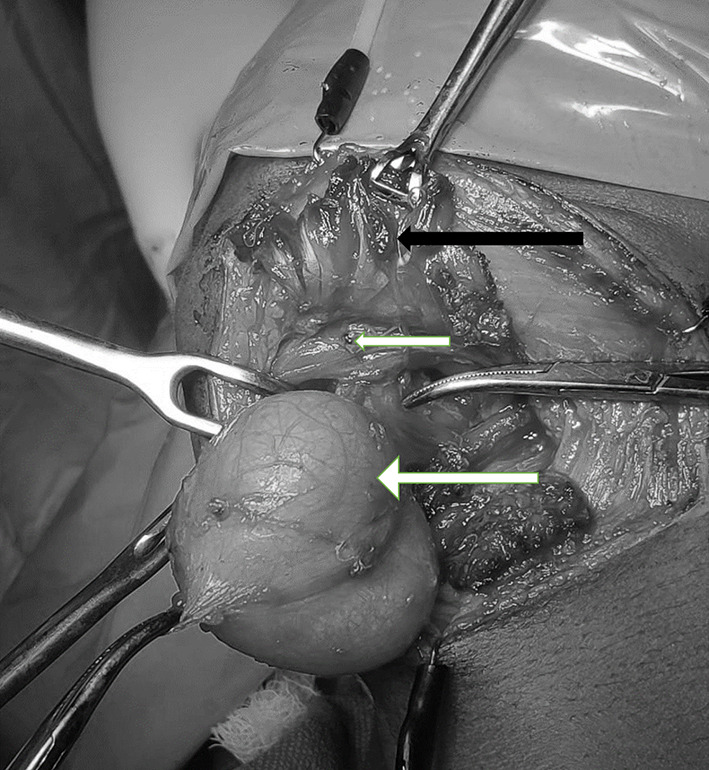

Fig. 2.

Cystic mass (Longer white arrow) noticed above mylohyoid (small white arrow) and geniohyoid. Digastric (black arrow) held up in Babcock forceps, mylohyoid fibres (small white arrow) separated to reach the lesion